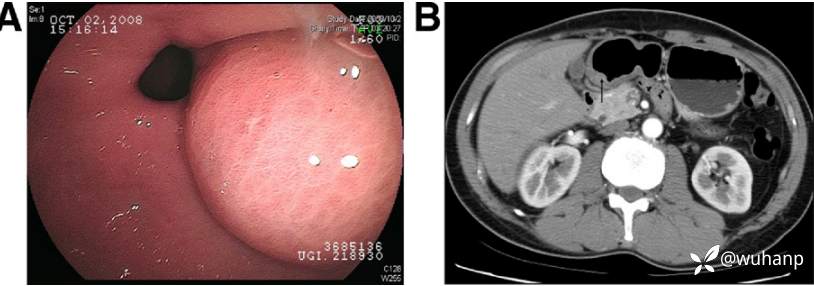

西兰花饺子 推荐患者男性,45岁,因上腹胀2周就诊,间断轻度上腹痛。既往史无特殊。

查体:体温正常,无黄疸,无外周淋巴结肿大。腹部无反跳痛。

辅助检查:WBC显著升高,转氨酶、胆红素、碱性磷酸酶均正常。

胃镜所见如下图(图A),腹部增强CT如下图(图B)。

请问:诊断是什么?

A 胃壁脓肿 B 胃囊肿 C 胃窦间质瘤 D 胃NET E 胆囊外压